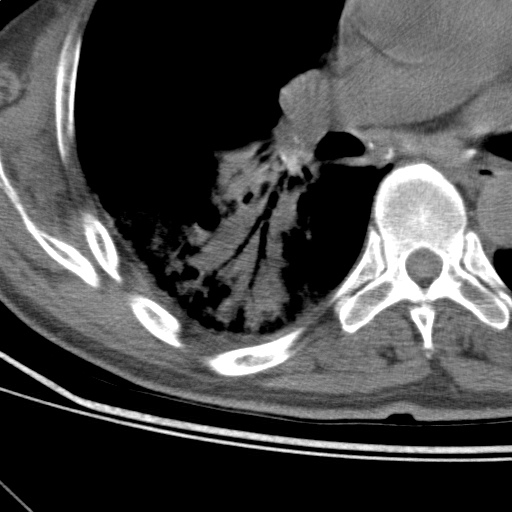

以下是引用随光逐影在2009-5-1 13:53:00的发言:[br]考虑为:1)两肺血行播散型肺结核;2)右肺下叶炎症感染。3)右侧胸膜增厚。